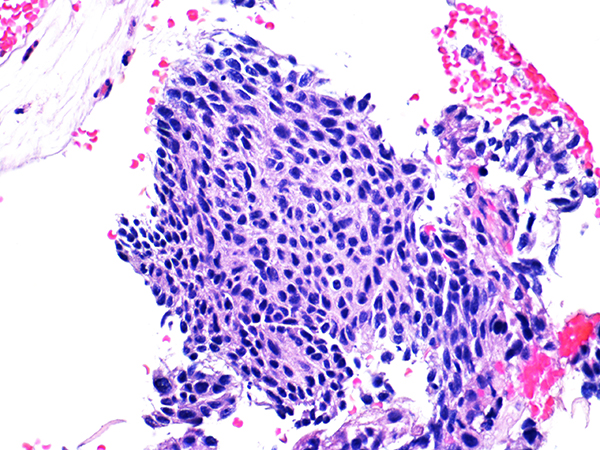

Soft Bx CIN 2 10x - Low Power

![]() Case 1

Area 1 - Soft Bx CIN 2 40x - High Power |